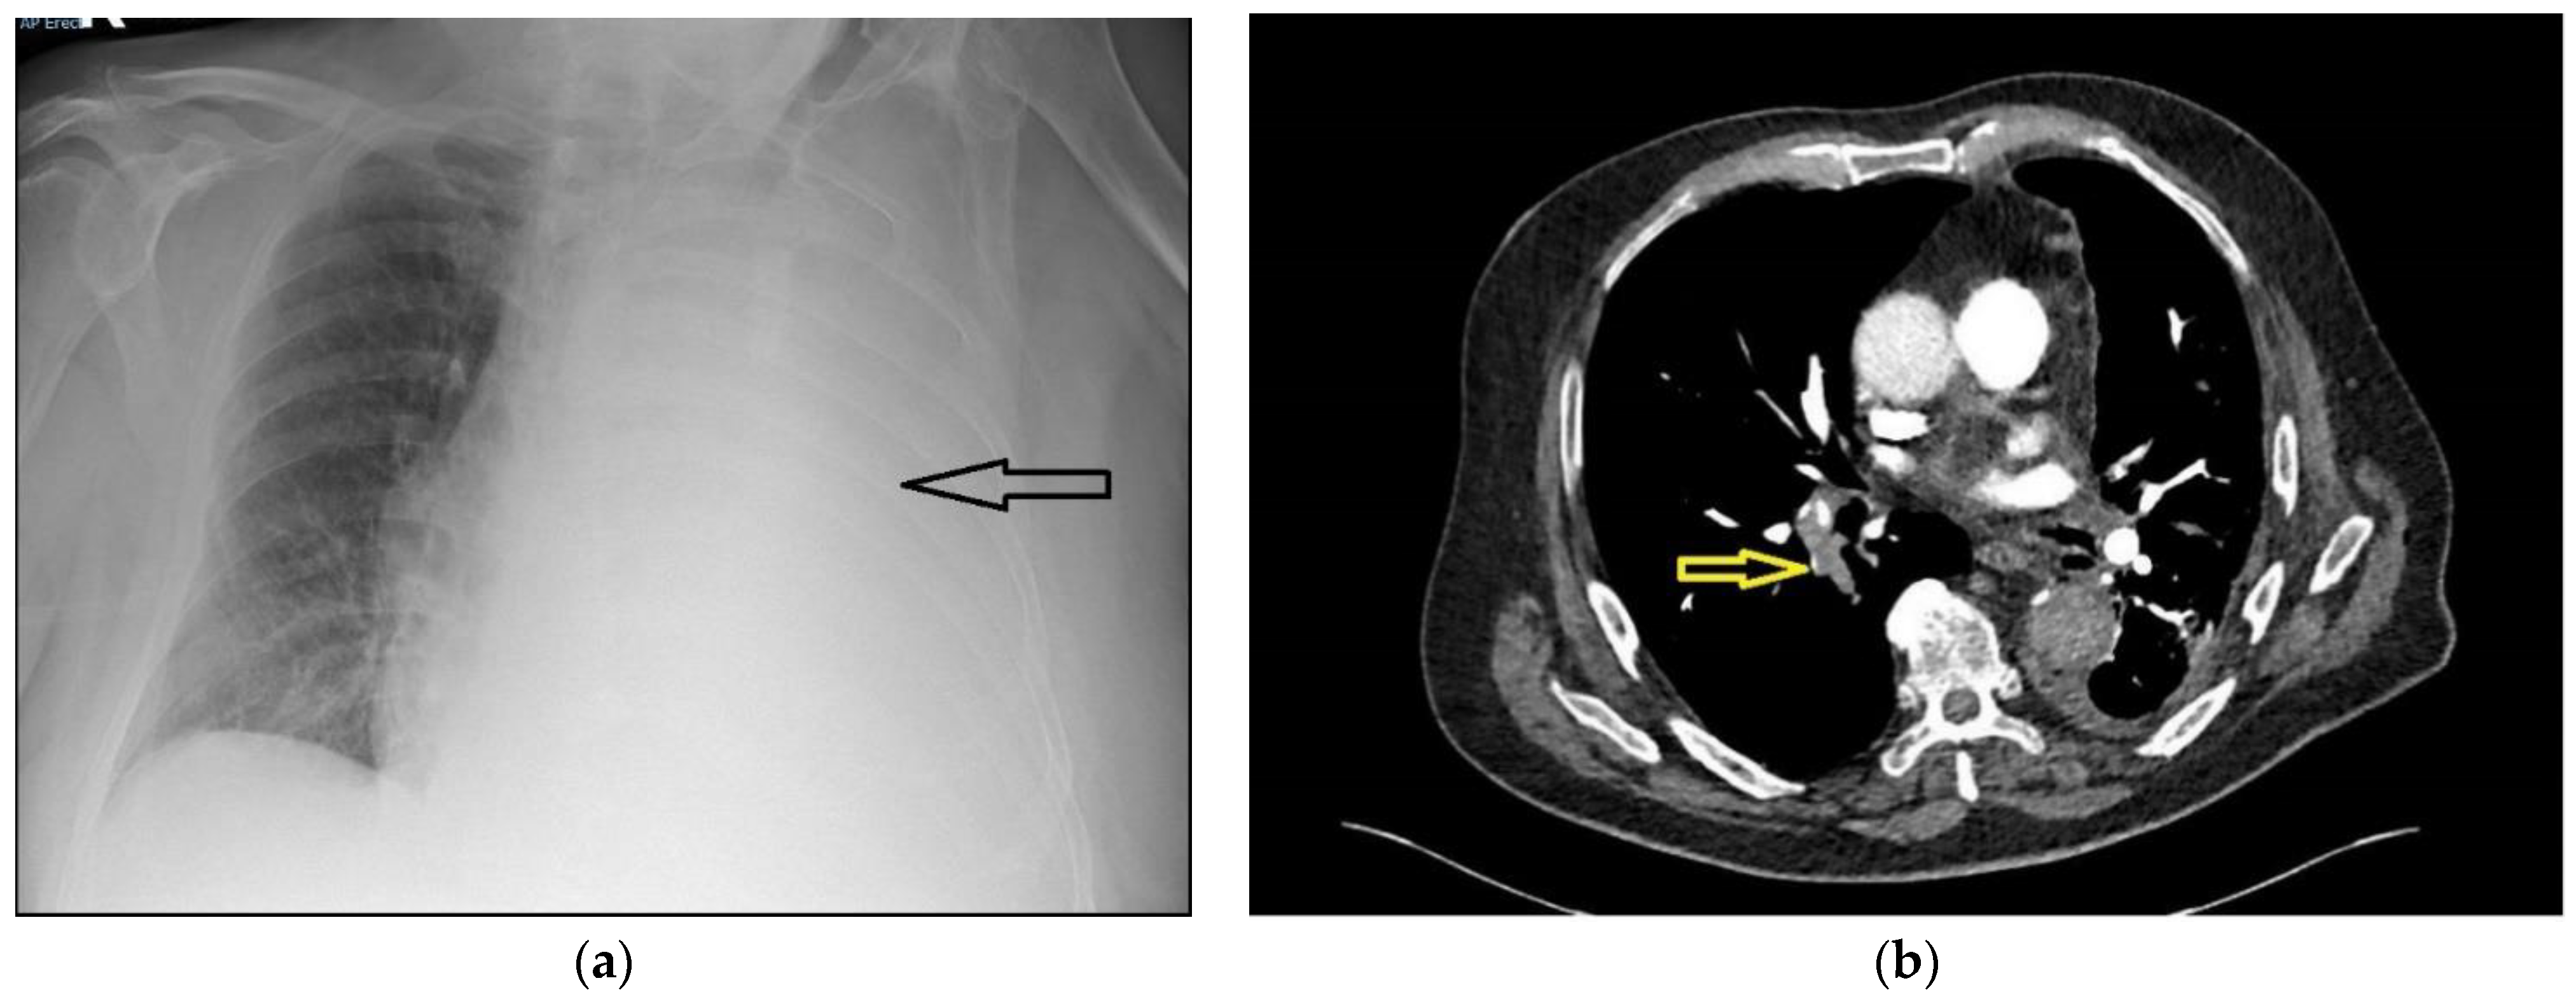

A 75-year-old male presented with a 5-day history of increasing dyspnoea. There were no red flag symptoms, and his past medical history only included treated hypertension. He was a life-long smoker of 62 pack-years. On assessment, he was normotensive, with a respiratory rate of 26 breaths per minute, pulse rate of 100 beats per minute, and saturations of 92% on 60% oxygen, measured using a Venturi mask. The arterial blood gas analysis showed type 1 respiratory failure (partial pressure of oxygen (PaO2) 8.1 Kilopascals, with a normal partial pressure of carbon dioxide (PaCO2)). A chest radiograph showed a large left pleural effusion (Figure 1a). A thoracic point-of-care ultrasound showed a large echogenic pleural effusion with lung collapse and a flattened diaphragm with normal motion. After discussion with the respiratory team, a small-bore chest tube was inserted under ultrasound guidance, and 4.2 L of blood-stained fluid was drained over the next 12 h. The patient’s respiratory rate became normal, his symptoms improved, and a repeat radiograph showed significant re-expansion of the lung field.

Figure 1. (a) Chest radiograph showing a large left-sided pleural effusion (marked with arrow); (b) slice of computed tomogram scan showing a right-sided pulmonary embolism (marked with arrow), small left-sided pleural effusion and pleural thickening consistent with a pleural malignancy.